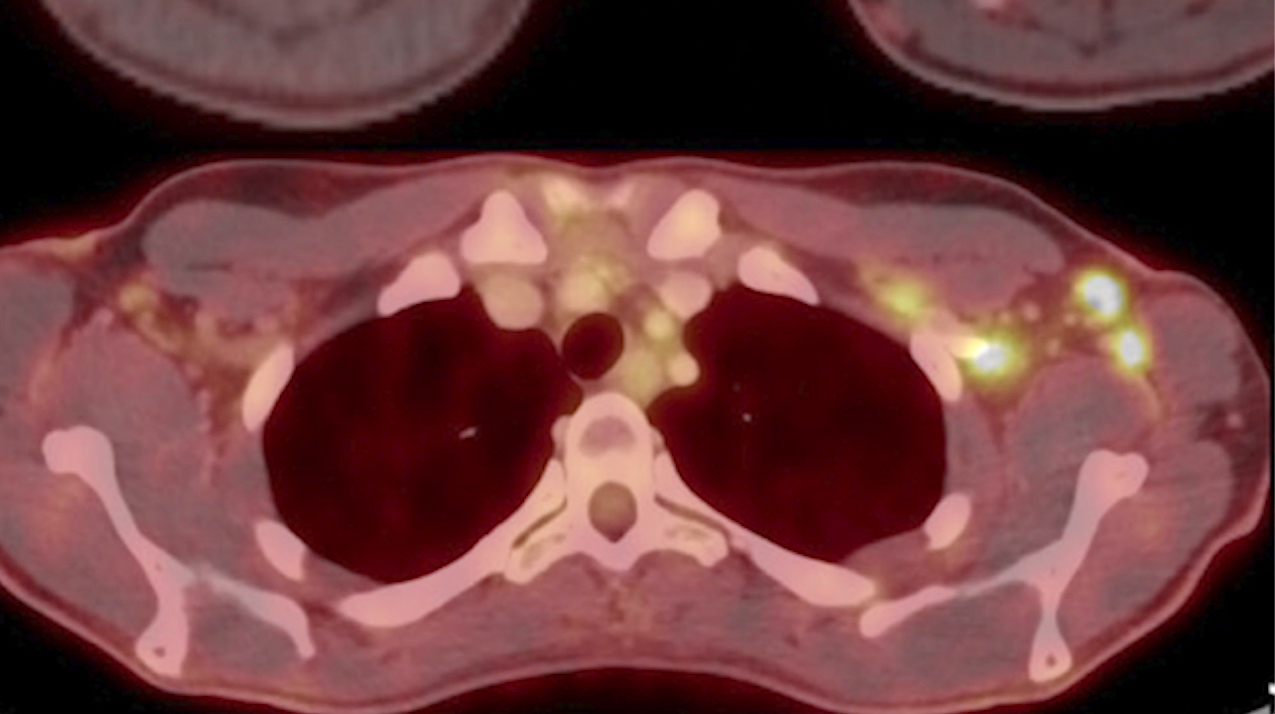

This photo gallery shows the variety of radiological presentations of COVID-19 (SARS-CoV-2) in medical imaging, including computed tomography (CT), radiograph X-rays, ultrasound, echocardiograms and magnetic resonance imaging (MRI). The radiology images show examples of typical COVID pneumonia in the lungs and the numerous complications the virus causes in the body in multiple organs, including the brain, kidneys, heart, abdomen and vascular system.

Ultrasound, especially hand-held ultrasound imaging devices, have become a primary imaging modality for novel coronavirus because of the ease to bag the device and sterilize it after use. CT and mobile X-ray systems are also used as front-line imaging systems for COVID-positive or suspected COVID patients.